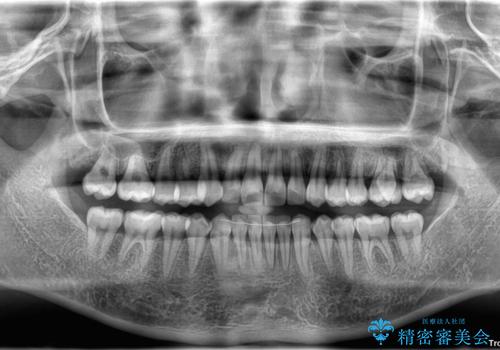

- 今回は「下の前歯のデコボコを治したい」と来院された患者様の症例をご紹介します。

診察してみると、下の前歯が並ぶためのスペースが足りないことが、歯並びがデコボコしている原因でした。

そこで今回は、以下の2つの方法を組み合わせて治療を行いました:

下の前歯の歯と歯の間をわずかに削ってスペースを作る(IPR)

奥歯を後ろに動かして、前歯が並ぶためのスペースを確保する

この計画により、デコボコだった下の前歯はしっかりと並び、わずか1年で治療を終えることができました